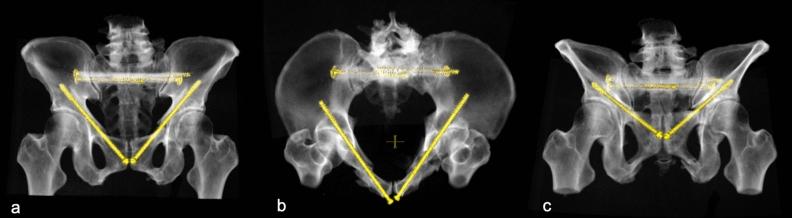

Retrograde transpubic screw fixation is a common procedure for the treatment of anterior pelvic ring fractures. With its sparing surgical approach and significant pain relief after screw fixations allowing early mobilisation, it has gained importance especially in the treatment of insufficiency fractures in elderly patients. However, positioning of transpubic screw osteosynthesis is not always possible due to narrowness and curvature of the screw corridor. The aim of the present study was to evaluate availability and length of the screw corridor using a 3D statistical model of the pelvic ring consisting out of 150 uninjured pelves. Virtual bore probes with a diameter of 7.5 mm were analysed as to accessibility, length and grey value distribution in Hounsfield Unit (HU). A transpubic corridor with a diameter of ≥ 7.5 mm was available in 185 of 300 investigated superior pubic rami with mean screw length of 131.7 mm. Accessibility of the screw corridor was higher in males than in females. However, screw length showed no systematic differences between the sexes or ethnicities. Analysis of the grey value distribution demonstrated the strongest bone to be located at the lateral ilium and the supraacetabular region.

经耻骨逆行螺钉固定是治疗前骨盆环骨折的常用方法。由于螺钉固定后手术入路狭窄,且能显著缓解疼痛,允许早期活动,因此该方法尤其在治疗老年患者的骨质疏松性骨折方面具有重要意义。然而,由于耻骨弓狭窄和弯曲,并非总能进行耻骨经皮螺钉固定。本研究的目的是使用由 150 个未受伤骨盆组成的骨盆环 3D 统计模型,评估使用 7.5mm 直径虚拟导针的可用性和螺钉通道的长度。分析了直径为 7.5mm 的经耻骨通道的可及性、长度和亨氏单位 (HU) 的灰度值分布。在 300 个研究的耻骨上支中,185 个有直径≥7.5mm 的经耻骨通道,平均螺钉长度为 131.7mm。男性的螺钉通道可及性高于女性。然而,螺钉长度在性别或种族之间没有系统差异。灰度值分布分析表明,最强的骨位于髂骨外侧和髋臼上方区域。